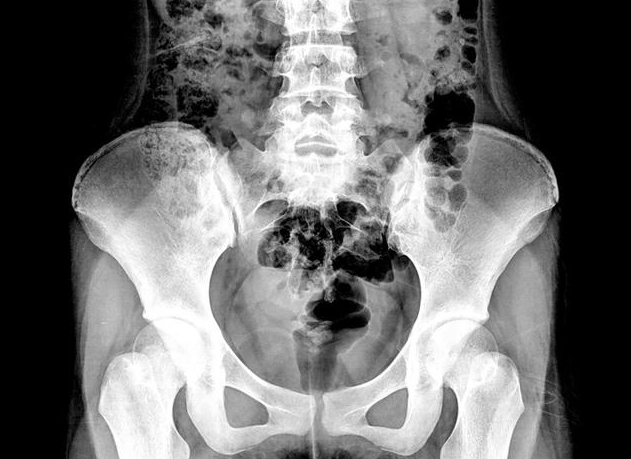

B超顯示盆腔積液并不一定就是盆腔炎的緣故,盆腔積液有生理性和病理性的,病理性的需要進(jìn)一步檢查治療,那么,盆腔積液和盆腔炎有什么關(guān)系?B超顯示盆腔積液怎么回事?下面八寶網(wǎng)小編就來(lái)說(shuō)說(shuō)。

盆腔炎的盆腔積液一般是由于炎癥刺激腹膜滲出導(dǎo)致的,沒(méi)有滲出并不代表沒(méi)有盆腔炎。盆腔炎的診斷除了B超外,還要結(jié)合婦科檢查,排除其它婦科(子宮內(nèi)膜異位癥、卵巢囊腫扭轉(zhuǎn)、黃體破裂、肌瘤變性等)或內(nèi)外科的疾病(闌尾炎、腸道疾病等等)才能明確診斷。

盆腔積液本身并不是一種疾病,它只是B超影像學(xué)檢查的一種表現(xiàn)。具體的說(shuō),有些盆腔積液是生理性的,主要有排卵期的卵泡液,月經(jīng)期的經(jīng)血也可能逆流進(jìn)入腹腔,這些盆腔積液,都是可以吸收的。